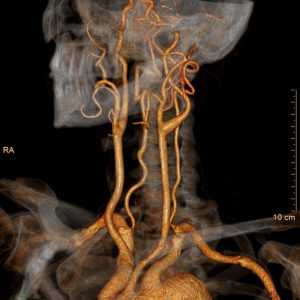

КТ-ангиография сосудов головы и шеи

КТ-ангиография сосудов головы и шеи считается важной частью обследования указанного участка тела. С ее помощью получается визуализировать текущее состояние здоровья не только крупных артерий. За счет детализированного изображения врач-рентгенолог сможет разобраться даже в изменениях сосудистых структур более мелкого калибра, если они имеют место быть.

Главной задачей данного современного исследования считается оценка кровотока по нескольким параметрам, а также поиск возможных патологий врожденного или приобретенного характера. Итоговая визуальная картина позволяет найти отклонения сосудов любого размера, начиная от их некорректного расположения и закачивания расширением или сужением их просвета. Все эти данные вместе гарантируют вынесение точного диагноза на ранней стадии развития недуга, что в будущем способствует скорейшему выздоровлению за счет правильно назначенной программы лечения.

Также обнаруженные на начальной фазе развития заболевания оказывают на организм меньше осложнений, что особенно актуально в случае поражения сосудов тяжелыми изменениями любого типа.

Суть методики

Обычно компьютерная томография обследуемого отдела организма, которую сами медики сокращают до аббревиатуры КТ, является лишь одной из составляющих исследования головы, мозга и шейного отдела. Методика получения высокоинформативной картины глубоких и неглубоких сосудов базируется на принципе послойного сканирования тканей с помощью рентгеновского излучения.

Все полученные данные суммируются с помощью компьютерной программы. Она дает рентгенологу подробную визуализацию, которая представляет собой объемную модель внутренних органов, крупных сосудов и капилляров. Чтобы снимок получился еще четче и с хорошей контрастностью, дополнительно используется стадия контрастирования. Она предусматривает введение контрастирующего препарата в кровь, что делает сосуды более выделяющимися на общем фоне.

Ангиография сосудов головного мозга

На сегодняшний день ангиография сосудов головного мозга — самый распространенный метод для диагностики нарушений кровообращения головного мозга особенно в диагностически запутанных случаях, а также перед осуществлением нейрохирургических операций.

Внешний вид сосудистого рисунка поможет диагностировать многие патологические процессы, включая опухоли, микроинсульты, кисты и другие. Существует ряд патологических состояний, при которых может потребоваться назначение церебральной ангиографии: